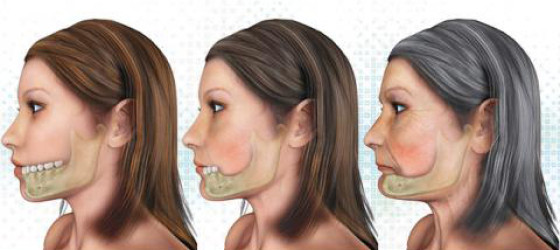

Augmentacija grebena je operativni zahvat kojim se nadomještava nedostatak kosti potreban za ugradnju implanta. U zavisnosti od područja i veličine defekta, koristi se nekoliko tehnika. Uzroci gubitka kosti mogu biti FIZIOLOŠKI, nakon vađenja zuba i usled starenja, i PATOLOŠKI, u koje spadaju parodontalne bolesti, kao i procesi u samoj kosti (granulom, cista, tumor). Gubitak kosti je prisutan i nakon oralnohirurških zahvata, traume, kao i dugotrajnog nošenja mobilnih proteza.

Nepravilnosti alveolarnog grebena u gornjoj i donjoj vilici mogu rezultirati nedostatkom koštane mase koja je potrebna za ugradnju implantata. Takve nepravilnosti mogu biti uzrokovane parodontozom, nošenjem proteza, razvojnim anomalijama ili povrijedama. Ne samo što takve nepravilnosti mogu uzrokovati probleme pri postavljanju implantata, već će stvoriti estetske probleme i onemogućiti optimalnu oralnu higijenu. Kako bi se ispravili takvi nedostaci kosti, greben se može augmentirati (povećati) koštanim nadoknadama.